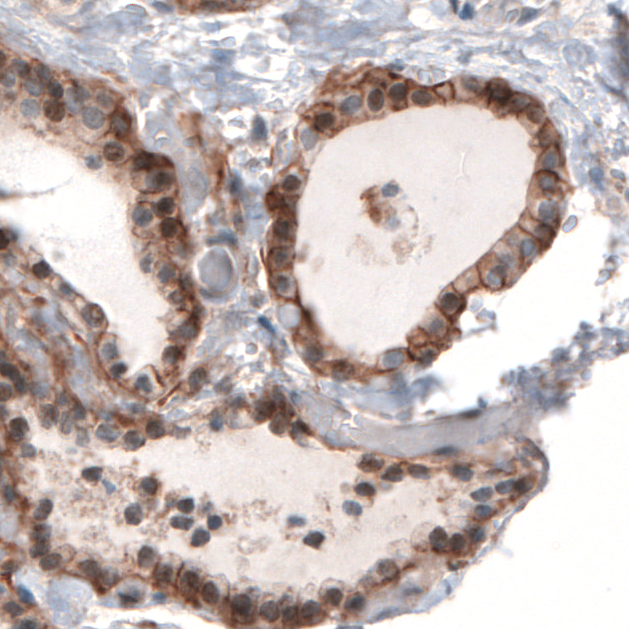

Immunohistochemical staining of human liver shows moderate to strong membranous positivity in hepatocytes.